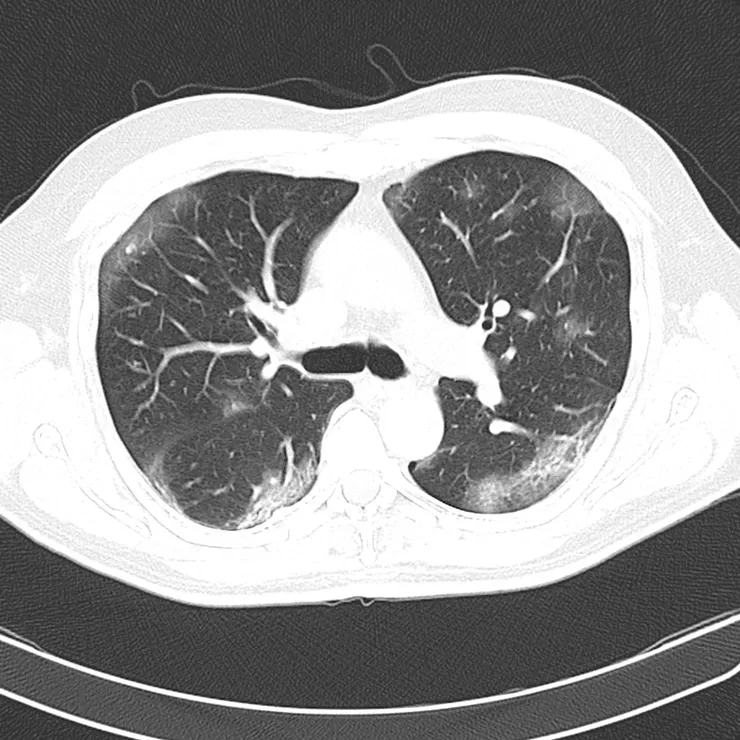

武漢研究

來自中國武漢的一項研究描述58位完全無症狀患者的CT掃描顯示 : 主要位於肺的外周(44%) 和肋膜下區域(75.9%),主要在一個 (38%) 或兩個肺葉(65.5%)。 肺部混濁是朦朧的白色雲層(CGO) 病變傾向於分佈在下葉(左62.1%, 右 68.9%)。而且58位完全無症狀患者,【94.8%】的CT掃描是有明顯病變。

研究人員觀察了鑽石公主號遊輪上乘客的CT掃描。在沒有咳嗽或發燒等症狀的76人中,有【54%】的人表現出明顯的肺部異常

特別是肺部浸潤。肺部浸潤似毛玻璃現象,形成了朦朧的白色薄雲層,與肺部的黑暗形成對比,這通常表明肺部充滿了發炎液體,來自細菌和免疫細胞戰爭後的成果。